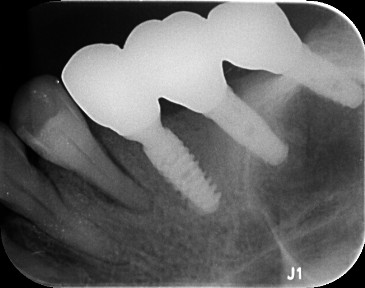

植入后 X 线照片

种植二期,拍片检查

术中戴牙拍片